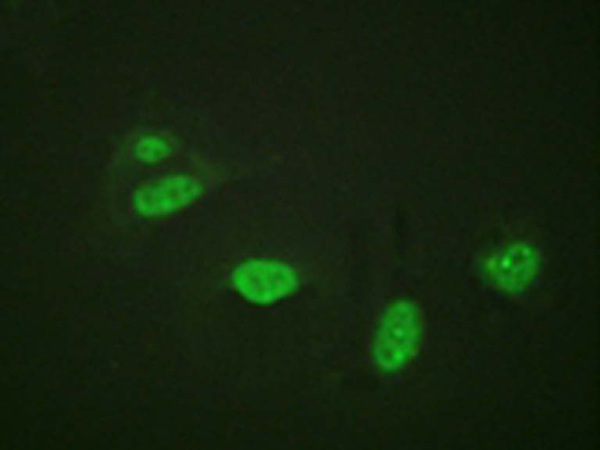

IF positive control: |

Hela cells |

IF Recommend dilution: |

100-200 |